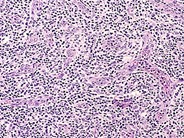

2015 july 3, luis f. J cancer res immunooncol 5: Angioimmunoblastic t cell lymphoma (aitl) presents in older patients and the median age at diagnosis is approximately 60. In aitl, the tumor cells are often accompanied by a mixed inflammatory infiltrate. Angioimmunoblastic lymphadenopathy (aild) with dysproteinemia;

Angioimmunoblastic t cell lymphoma (aitl) is a peripheral t cell lymphoma characterized by systemic disease, a polymorphous infiltrate involving lymph nodes, and a prominent proliferation of.

In aitl, the tumor cells are often accompanied by a mixed inflammatory infiltrate. Blood diseases, cancer diseases, immune diseases, rare diseases. Angioimmunoblastic t cell lymphoma microenvironment. 2015 july 3, luis f. Angioimmunoblastic lymphadenopathy (aild) with dysproteinemia;